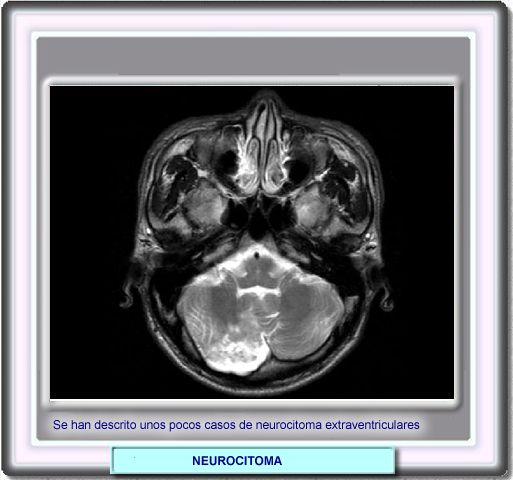

Neurocitoma localizado en la porción inferior media del cerebelo. En este caso, el tumor iba acompañado de dolor de cuello.

La microscopìa electrónica puso de manifiesto la presencia de procesos citoplasmáticos conteniendo densos gránulos secretores y túbulos